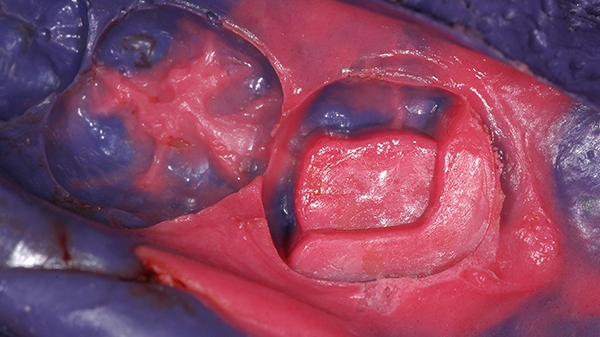

La rilevazione dell'impronta della cavità e dell'arcata dentaria è condotta mediante polietere da impronta e la cavità preparata ha subito temporizzazione per mezzo di materiale da otturazione provvisoria a base resinosa.

La rilevazione delle caratteristiche cromatiche dei denti adiacenti è avvenuta con l'ausilio di scala cromatica vita.

Un consulto con l'odontotecnico il giorno successivo, allo sviluppo dell'impronta, ha permesso di decidere la natura del materiale ceramico con il quale realizzare il restauro.

In considerazione dell'estensione del restauro, delle notevoli sollecitazioni meccaniche alle quali l'elemento dentale è sottoposto e alle caratteristiche cromatiche dei denti vicini si è scelto per realizzare il restauro con una ceramica vetrosa a base di di-silicato di Litio manipolata mediante presso-fusione.